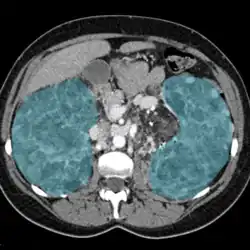

Enlarged kidneys in blue

Nephromegaly is the process whereby one or both kidneys become enlarged. It is defined as an enlargement of more than two standard deviations above the mean for age and body size of a particular individual. It can be caused by a variety of conditions including infiltrative disorders, metabolic conditions, cysts, and other diseases.

Nephromegaly is the process whereby one or both kidneys become enlarged.[2] It is defined as an enlargement of more than two standard deviations above the mean for age and body size of a particular individual. In adults, as the normal kidney length is typically 10–12 cm (3.9–4.7 in), lengths above 13 cm (5.1 in) suggest a general enlargement.[3][4]